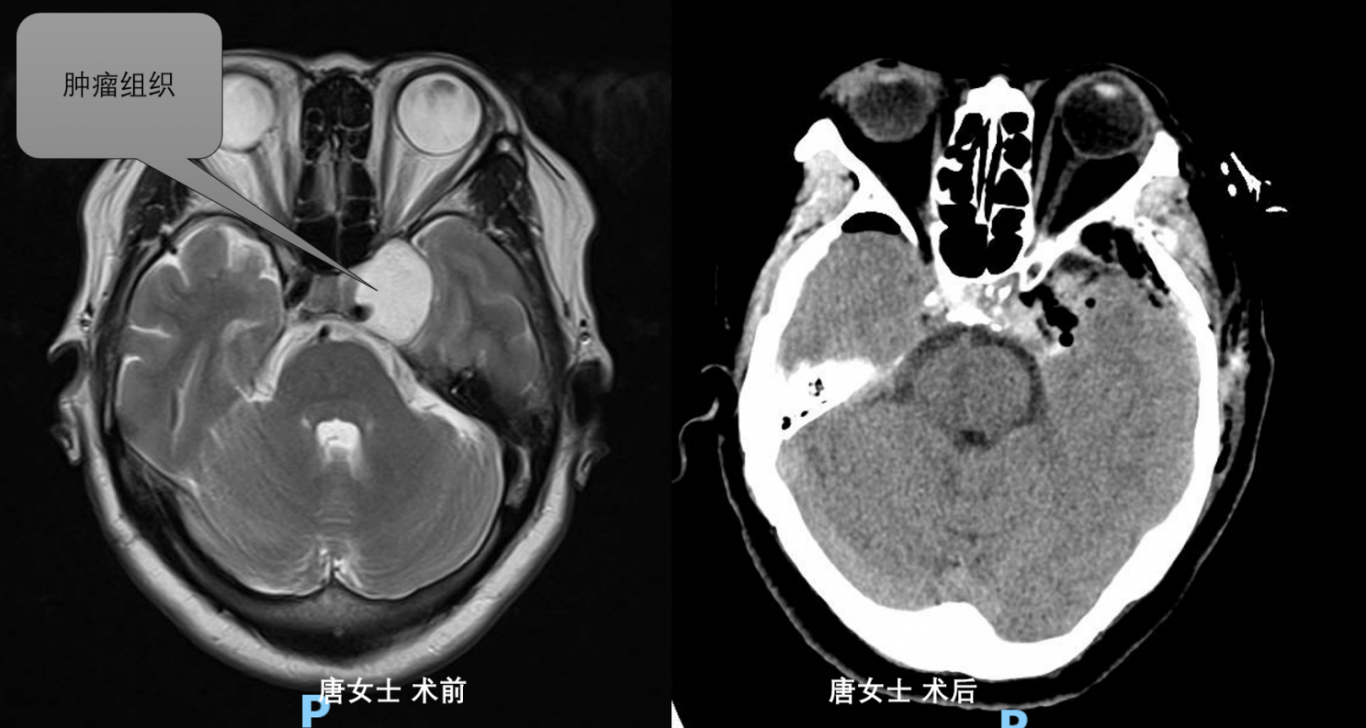

案例三:

龍馬潭區(qū)唐女士因左眼視物不清,入院后檢查提示鞍區(qū)占位。術(shù)后病檢提示海綿狀血管瘤。